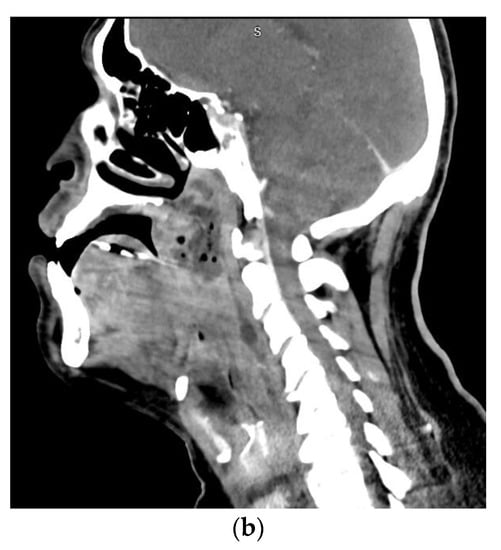

A feared complication of severe odontogenic infections is airway obstruction. When these infections involve deep fascial spaces, significant airway narrowing, and deviation may occur. Of particular importance is Ludwig’s angina which involves the submental space, the bilateral submandibular spaces, and the bilateral sublingual spaces Figure 2. The mandibular molars are the most common sources of infection leading to Ludwig’s angina. The clinical presentation includes pain, drooling, dysphonia, brawny neck edema, and tongue protrusion or elevation. The tongue is often pushed up and backward due to the fascial spaces involved, leading to airway obstruction. With improved imaging techniques, antibiotics, and a shift to early surgical treatment, the mortality rate from Ludwig’s angina has decreased from 50–54% to around 4–8% [,,].

Figure 2.

Axial (a) and sagittal (b) computed tomography scan views of a patient with Ludwig’s angina.